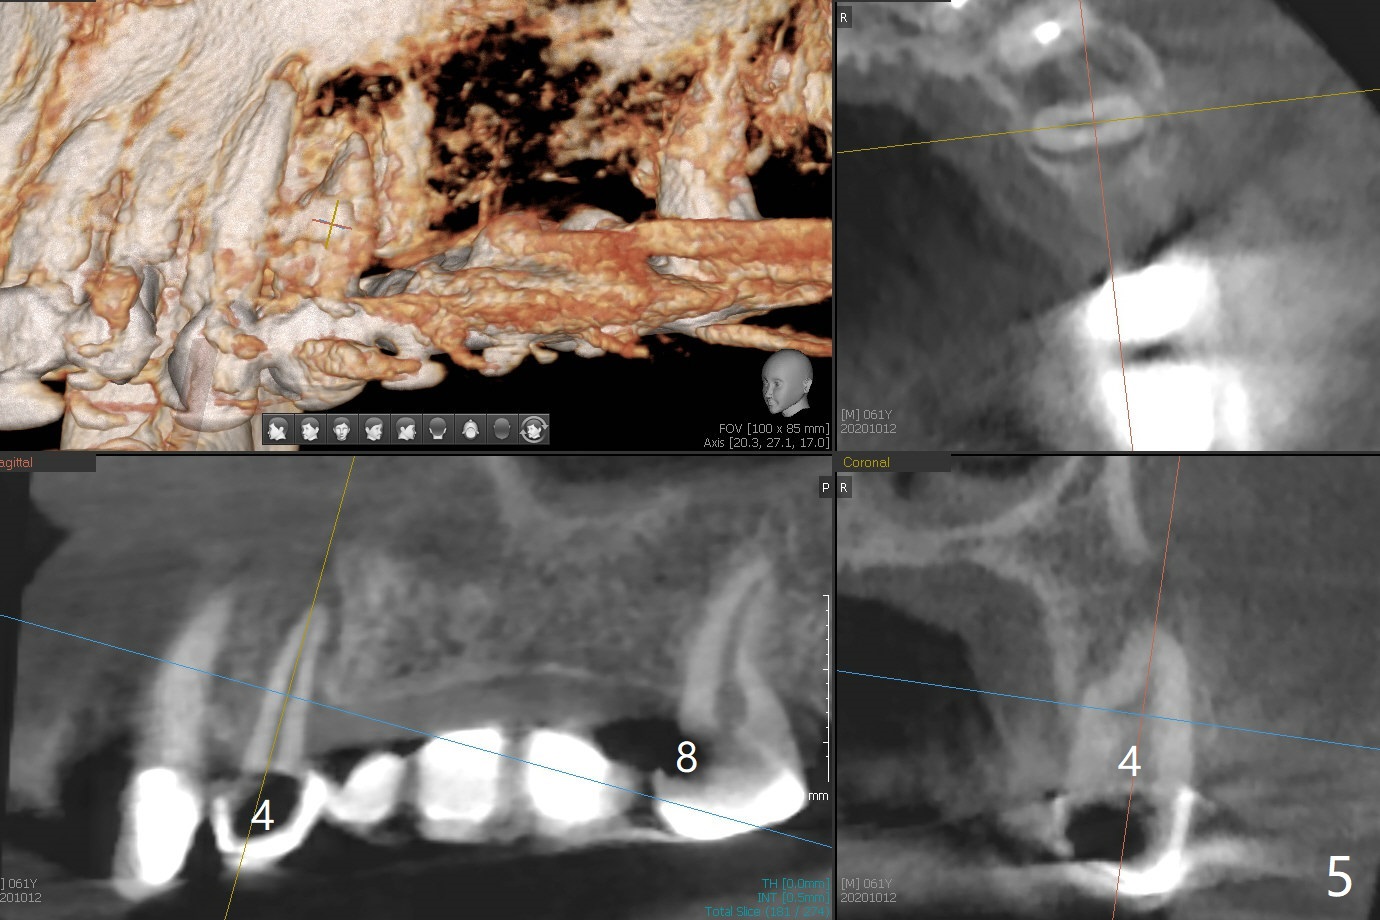

61男牙齿不好,左上4-8牙桥松动(图一,五,六),右下2,左下3根尖瘘道(图二),左上4,8也需要根管治疗,以上牙齿以及右下3插入球状牙桩(图一:*),然后在右上,左下,右下7植牙,放置球状基台(图一:箭头),固定上下活动义齿(覆盖义齿)。下前牙颊侧骨板几乎没有(图七)。左下7骨头(图八)宽于左下5(图三)。